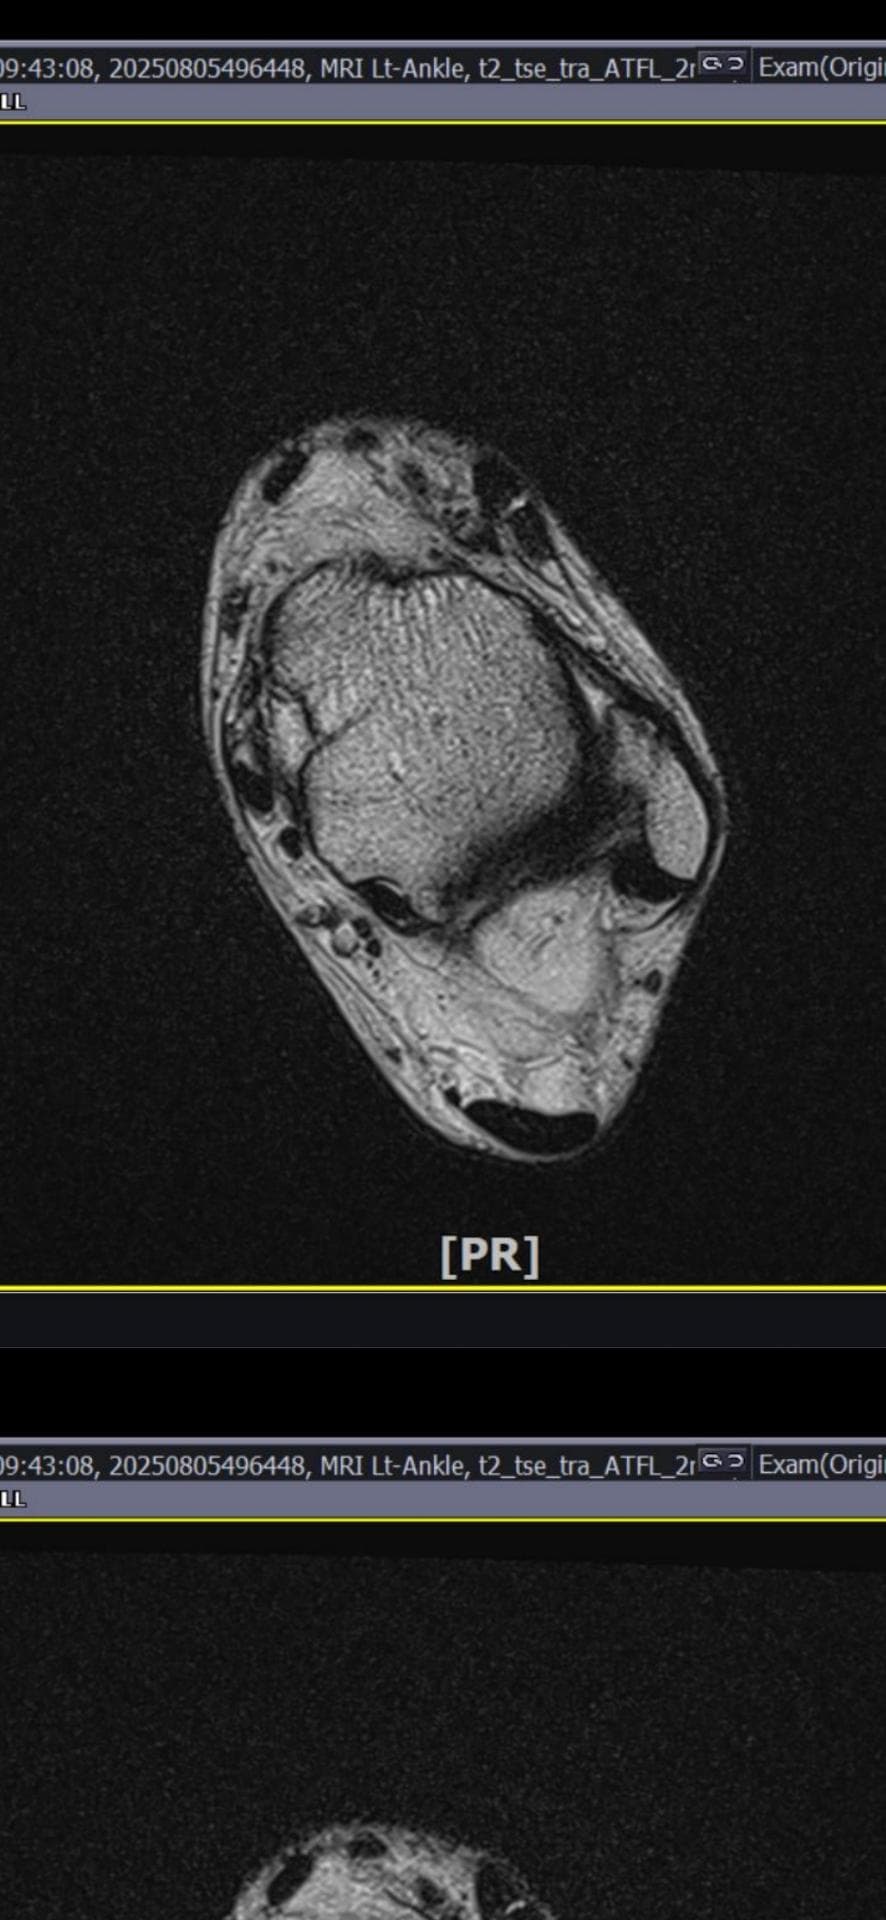

그런데 다친 지 2주 뒤부터 발목이 쑤시듯 아파 병원에서 초음파 검사를 했고, 전거비인대(ATFL) 2도 염좌 진단을 받았습니다. 이후 약 6주 동안 주 1회씩 충격파, 물리치료, 도수치료 등을 받았습니다. (고정치료는 시기가 늦었다며 진행하지 않았습니다.)

그래도 통증이 남아 8월 5일에 MRI를 촬영했는데, 병원에서는 “인대는 이어져 있고, 이 정도면 재활운동으로 호전될 것”이라는 설명을 들었습니다.

올려주신 mri를 보면 전거비인대는 연속성이 유지되고 있고 파열이나 큰 손상 흔적은 없어 재활로 회복 가능한 상태로 보입니다 다만 3개월 가까이 활동 시 통증과 미열감이 남아 있는 것은 조직 회복이 아직 완전히 끝나지 않았거나 주변 연부조직 관절 움직임 제한 등으로 인한 과민 반응일 수 있습니다.

초음파와 비교하면 mri 상으로 인대 연속성이 확인되므로 심각한 악화나 재파열은 아닌 것으로 판단됩니다